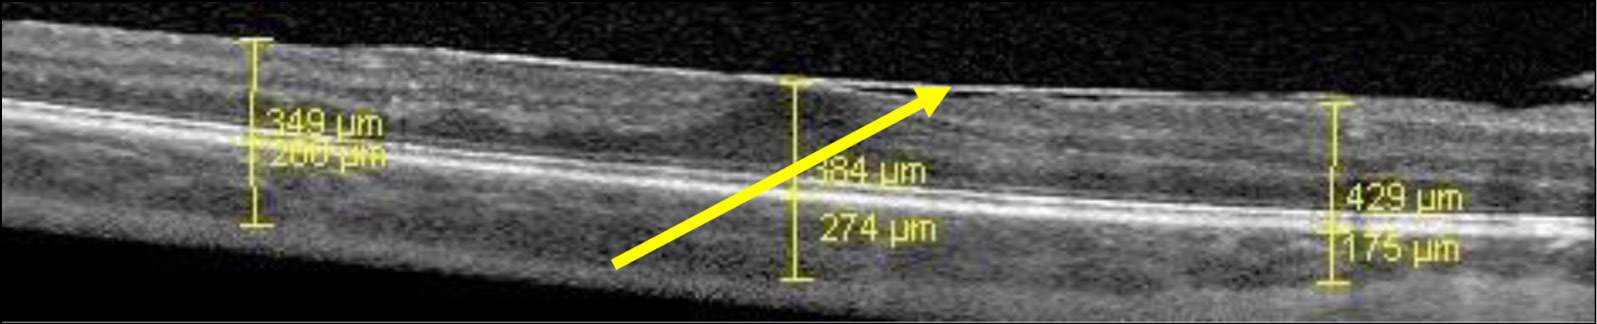

Утолщение сетчатки было зарегистрировано у пациентов с активным увеитом в 83% наблюдений, с вялотекущим — в 71%, с субактивным — в 55%, и было, очевидно, обусловлено накоплением в ней жидкости (отеком). При качественном анализе явный диффузный макулярный отек (утолщение сетчатки с наличием в ней мелких кистовидных полостей по типу «губки») был выявлен нами у 7 пациентов (26 наблюдений, 24%) (рис. 1), кистовидный (выраженное утолщение сетчатки за счет формирования кистовидных полостей большого размера) — у 2 пациентов (3 наблюдения, 3%) (рис. 2).

Рис. 1. Пациентка Л. ОКТ макулы, активный увеит, диффузный макулярный отек.

Примечание: Стрелками обозначено гипорефлективное пространство между наружной пограничной мембраной и наружным плексиформным слоем, расширенное за счет отека, сетчатка имеет вид «губки» за счет микрокист. Фовеолярный профиль несколько сглажен, толщина сетчатки увеличена.